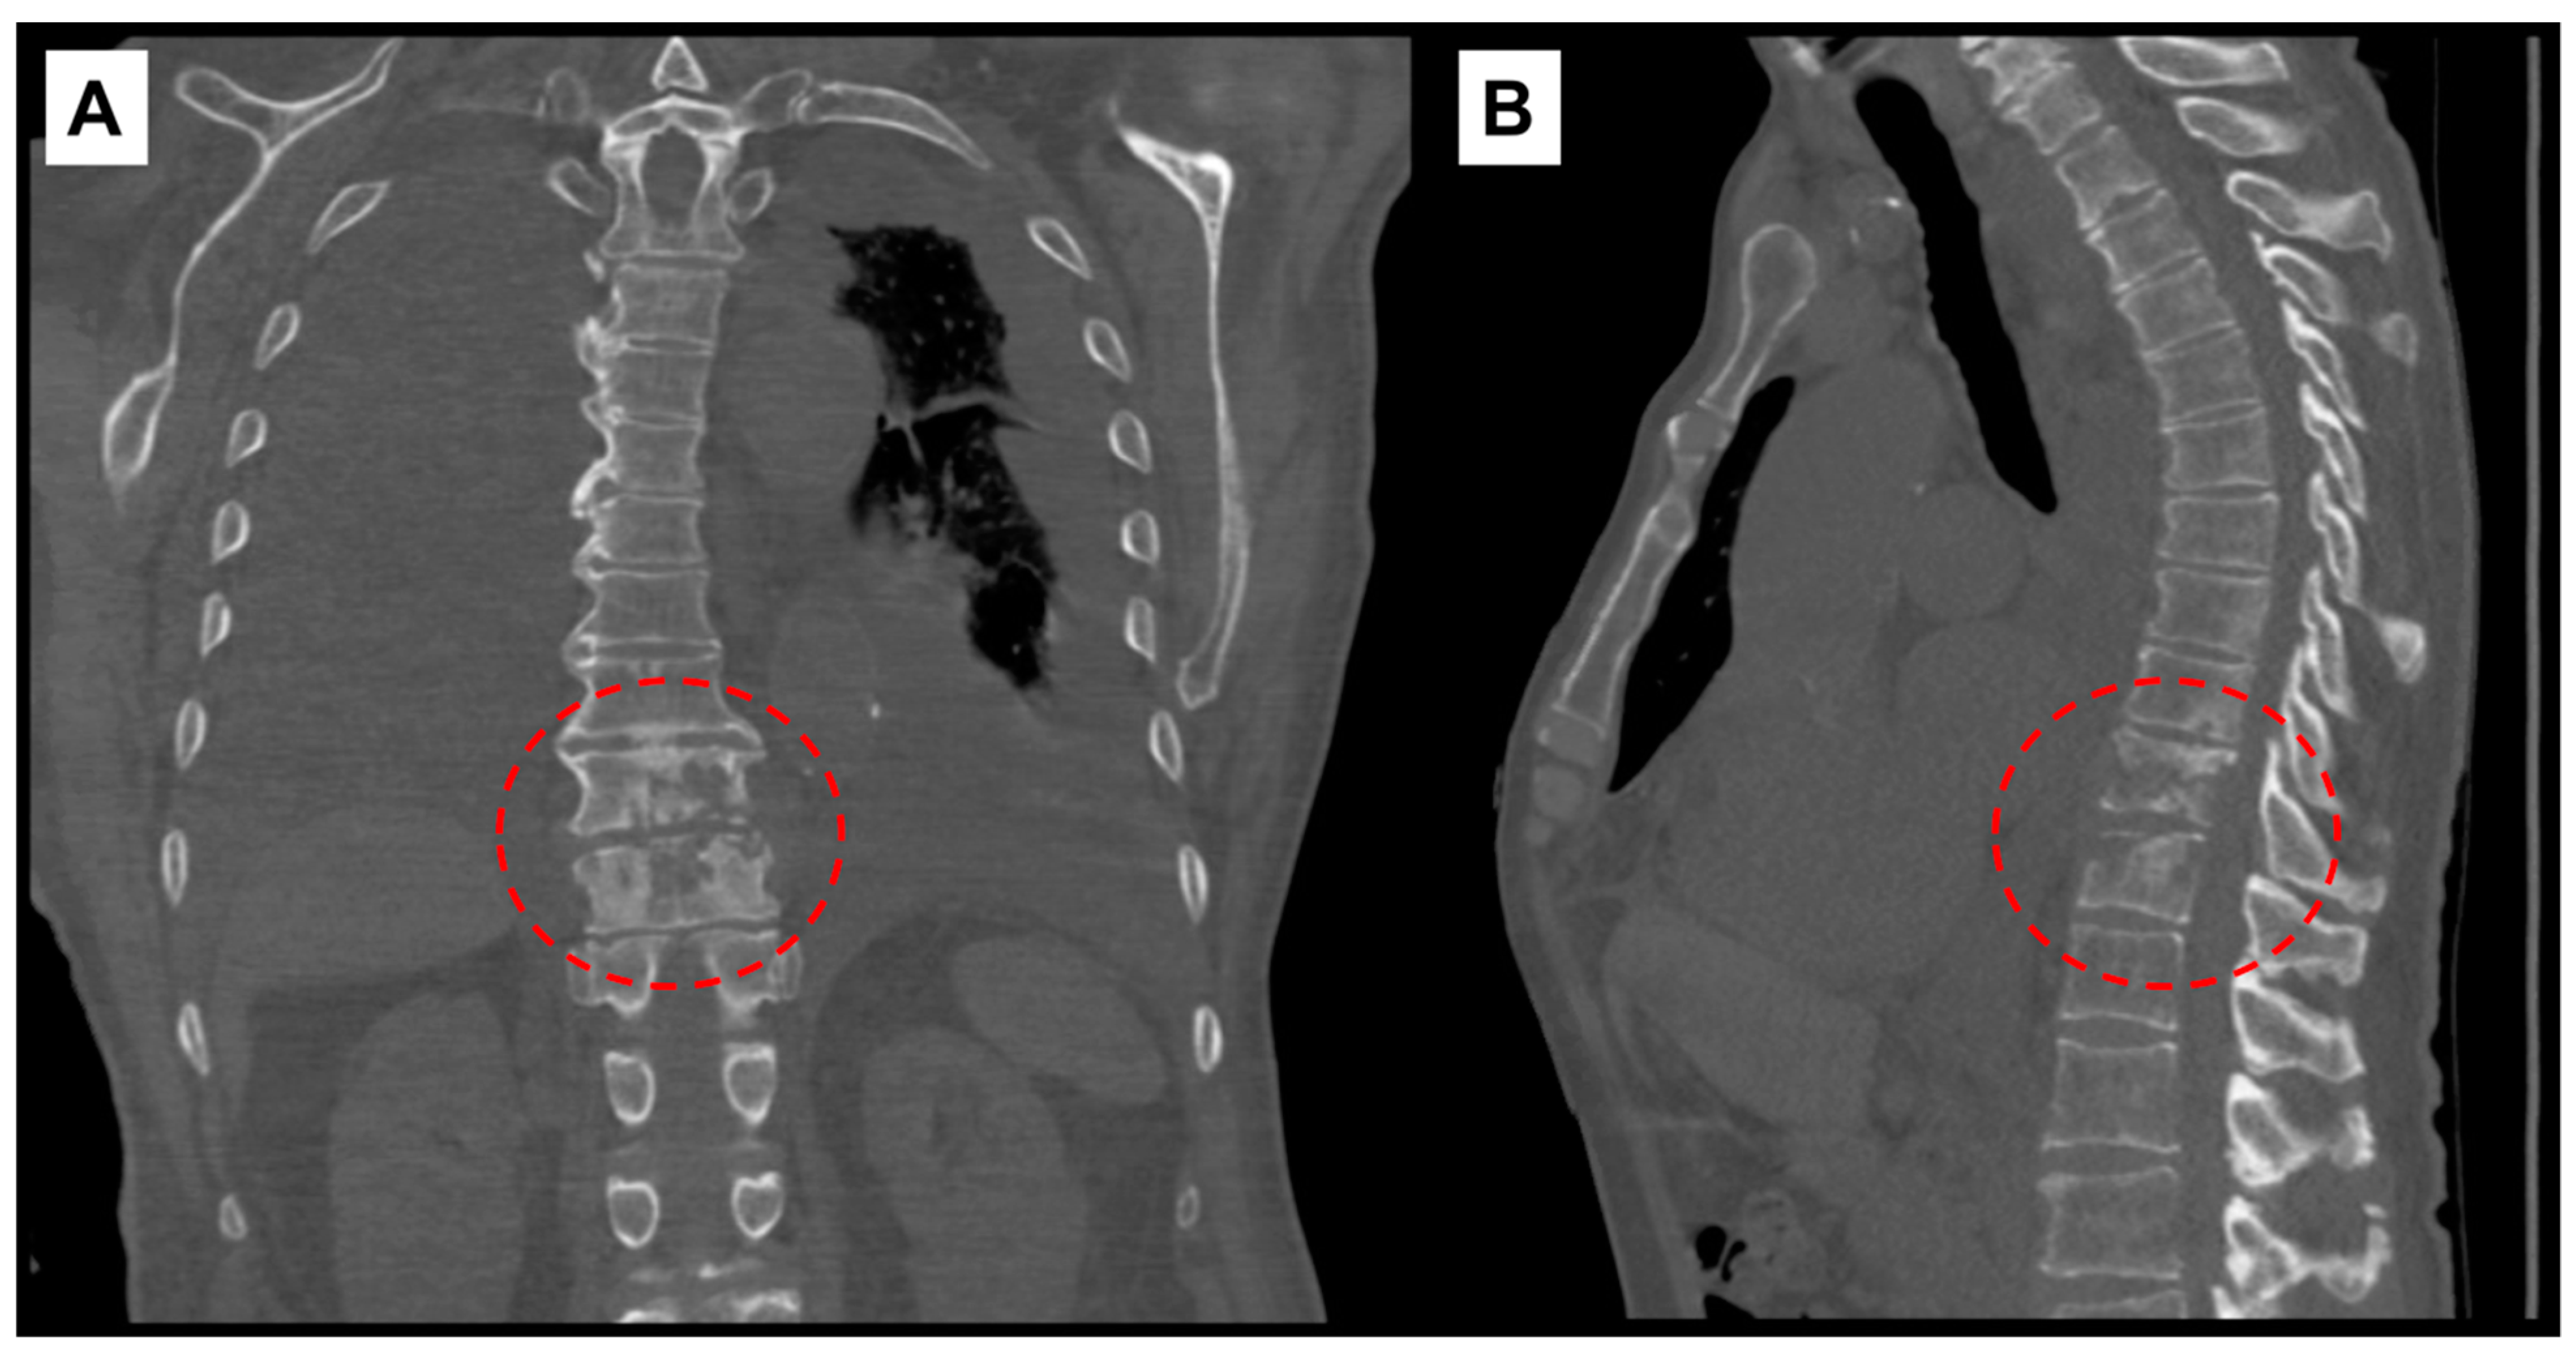

The following day, additional studies revealed elevated pro B-type natriuretic peptide (2337 pg/mL; ref. range: <300 pg/mL), sedimentation rate (39 mm/hr; ref. range: 0–20 mm/hr), and high sensitivity C-reactive protein (hsCRP) (69 mg/L; ref. range: 0.1–3 mg/L). A CT scan of the chest without contrast demonstrated findings compatible with discitis and osteomyelitis at T10–T11 level (Figure 1), moderate to large bilateral pleural effusions with associated compressive atelectasis of the adjacent lower lobes, consolidation of the right middle lobe, cardiomegaly, a small pericardial effusion, lung nodules measuring up to 1 cm, scattered calcified granulomas, and mildly enlarged intrathoracic lymph nodes.

Figure 1. Computed-tomography scan of chest showing T10–T11 discitis and osteomyelitis. (A) Coronal view with red, interrupted circle highlighting destructive changes to vertebral bodies. (B) Sagittal view.